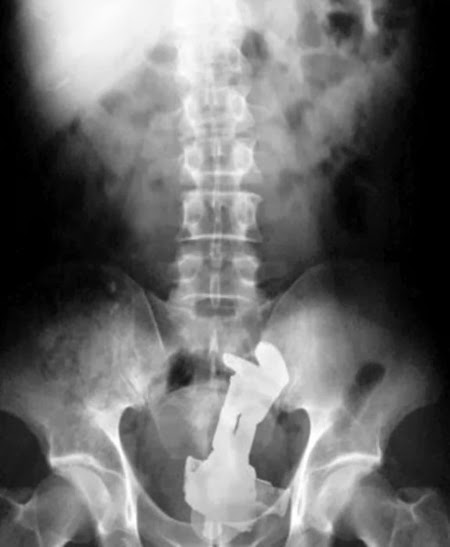

Radiografías de objetos extraños insertados en el ano